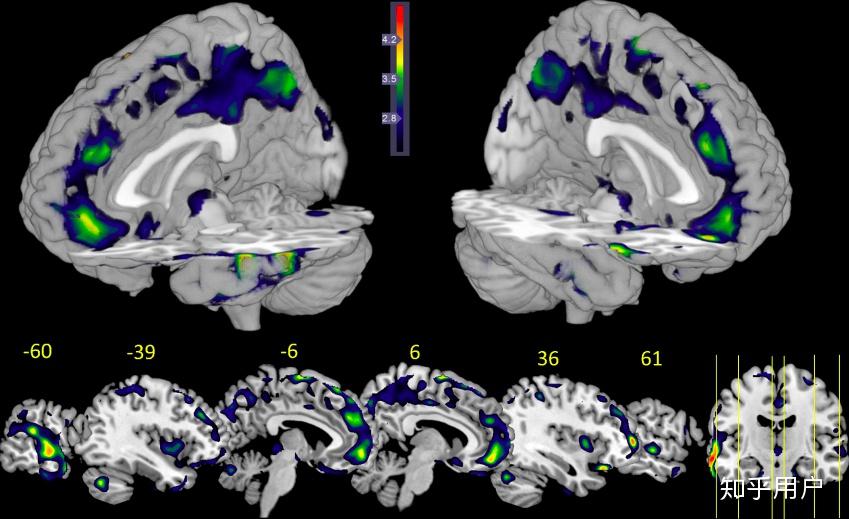

图片说明:图中蓝色区域为大脑灰质.